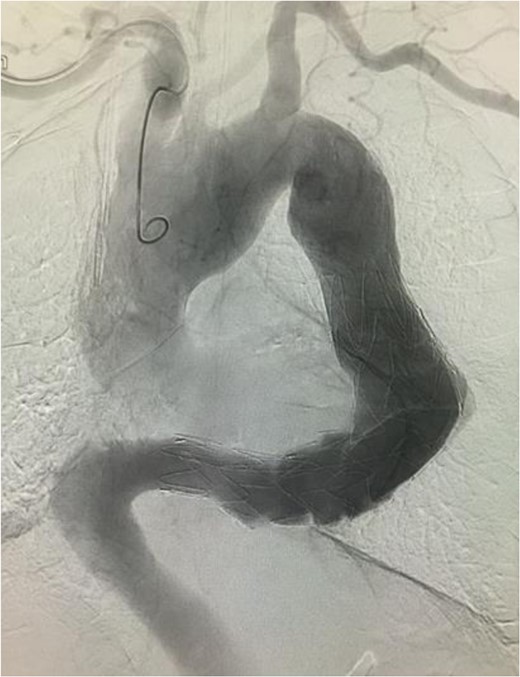

The stent graft (Relay Plus® 38 × 34 × 200 mm, Bolton medical, Barcelona) was introduced through the right common femoral artery. When it reached the distal site of the thoracoabdominal aorta where the angulation was the most severe, the outer hard sheath was left there while the inner flexible sheath was advanced. The flexible sheath was successfully introduced to the proximal site of the thoracoabdominal aorta beyond the angulation (Fig. 3). The stent graft was placed and we confirmed that no endoleak existed (Fig. 4).

Angiographic image at the completion of treatment. No endoleak was observed. There was no contrast enhancement in the location of the aneurysm.